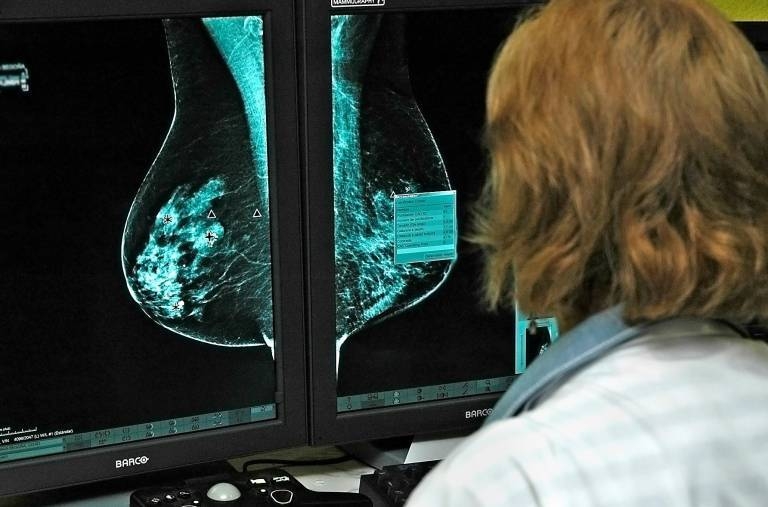

CASTELLÓ (EP). La Unidad de Mama del Hospital General Universitari de Castelló ha publicado un manual médico sobre senología y patología mamaria en

las personas trans que tiene como objetivo servir de guía clínica para el abordaje diagnóstico y terapéutico en estas enfermedades entre el colectivo LGTBI.